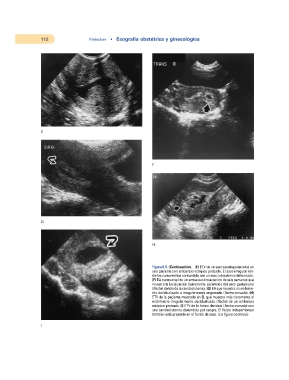

Figura 6-6. (Continuación). (E) ETV de un saco seudogestacional en

una paciente con embarazo ectópico probado. El saco irregular (en-

tre los cursores) fue confundido con un saco intrauterino deformado.

(F) EA transversal de un embarazo intrauterino de seis semanas que

muestra la localización típicamente excéntrica del saco gestacional

(flecha) dentro de la cavidad uterina. (G) EA que muestra un endome-

trio decidualizado e irregularmente engrosado (flecha curvada). (H)

ETV de la paciente mostrada en G, que muestra más claramente el

endometrio irregularmente decidualizado (flecha) de un embarazo

ectópico probado. (I) ETV de la forma decidual (flecha curvada) con

una cavidad uterina distendida por sangre. El fluido intraperitoneal

también está presente en el fondo de saco. (La figura continúa.)